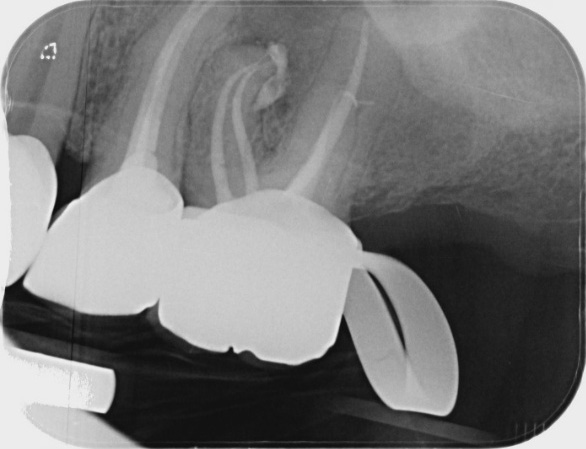

Pre-operatieve radiograph show an apical radiolucency on the mesiobuccal root and a small one on the discobuccal root. Diagnosis was apical abces due to pulpal necrosis.

A root canal treatment in one visit was performed through te crown. Four canals were treated. All canals were instrumented with Edge-One-R files (R25 for the buccal canals, R50 for the palatal canal).

Initial XR